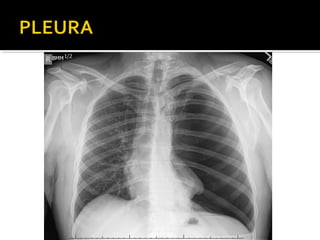

Este documento fornece parâmetros técnicos para realizar uma radiografia de tórax, incluindo posicionamento correto do paciente, dose adequada de radiação e estruturas anatômicas a serem avaliadas, como coração, pulmões, pleura, diafragma e ossos do tórax.